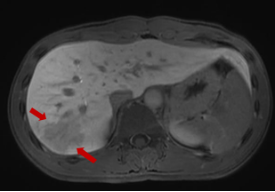

磁共振显示:肝右叶包膜下见多处团片状、楔形病灶,大者位于S7段,范围约2.7cm×1.8cm,部分病灶内见门静脉穿行,门脉血管无阻塞或异常征象,边界欠清。提示:肝右叶包膜下多发异常信号。